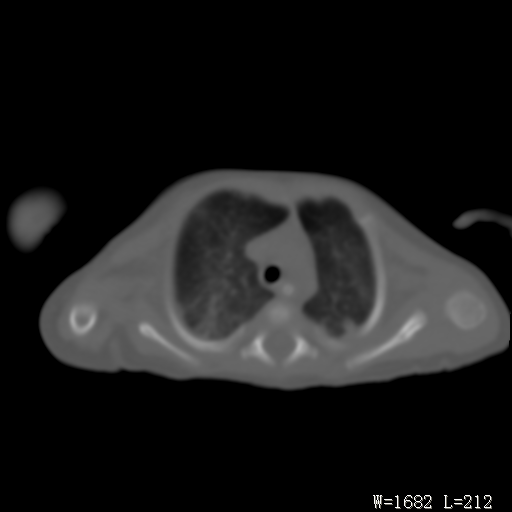

以下是引用改行者在2010-7-8 22:13:00的发言:[br]两肺野透光度降低伴细颗粒状影,两肺下叶见实变影,其内见支气管充气征。 多考虑新生儿肺透明膜病。